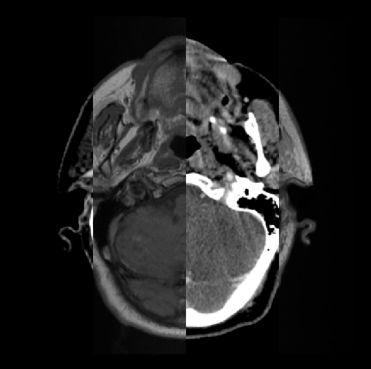

Organ at risk (OAR) segmentation is a critical process in radiotherapy treatment planning such as head and neck tumors. Nevertheless, in clinical practice, radiation oncologists predominantly perform OAR segmentations manually on CT scans. This manual process is highly time-consuming and expensive, limiting the number of patients who can receive timely radiotherapy. Additionally, CT scans offer lower soft-tissue contrast compared to MRI. Despite MRI providing superior soft-tissue visualization, its time-consuming nature makes it infeasible for real-time treatment planning. To address these challenges, we propose a method called SegReg, which utilizes Elastic Symmetric Normalization for registering MRI to perform OAR segmentation. SegReg outperforms the CT-only baseline by 16.78% in mDSC and 18.77% in mIoU, showing that it effectively combines the geometric accuracy of CT with the superior soft-tissue contrast of MRI, making accurate automated OAR segmentation for clinical practice become possible. See project website https://steve-zeyu-zhang.github.io/SegReg